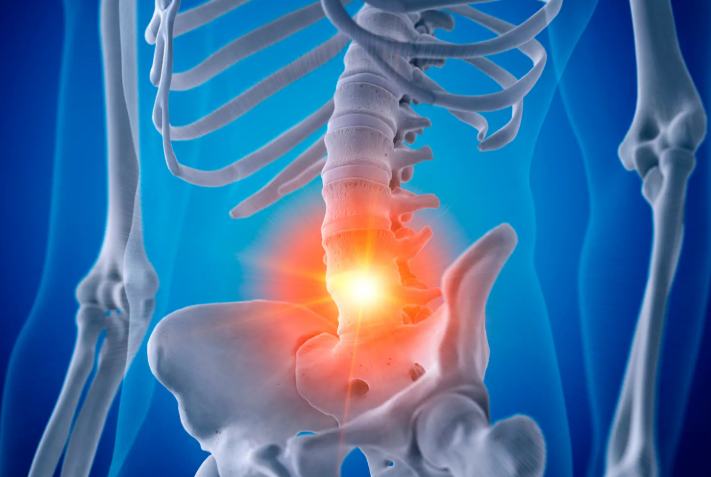

3. 통증과 기능적 제약

통증이 단발적인지, 지속적인지, 일상생활에 어떤 영향을 주는지를 평가합니다. 예를 들어 오랜 시간 서 있거나 앉아 있을 때 허리나 엉덩이 통증이 심해지는 경우, 장애등급 평가에서 불편함의 빈도와 강도 모두가 반영됩니다.

강직성 척추염은 관절 외에도 흉곽, 폐, 심혈관계 등에 영향을 미칠 수 있습니다. 흉곽이 경직되어 호흡이 제한되거나, 관절 이외의 염증 증상이 지속될 경우 등급 평가 시 함께 고려됩니다.